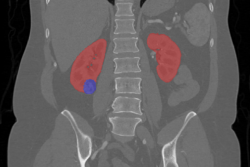

Thận là một bộ phận có vai trò quan trọng trong hệ tiết niệu, gồm có hai bên đối xứng nhau và có hình hạt đậu. Thật có nhiệm vụ giúp cơ thể loại bỏ chất thải và lọc máu trước khi đưa máu trở lại tim.